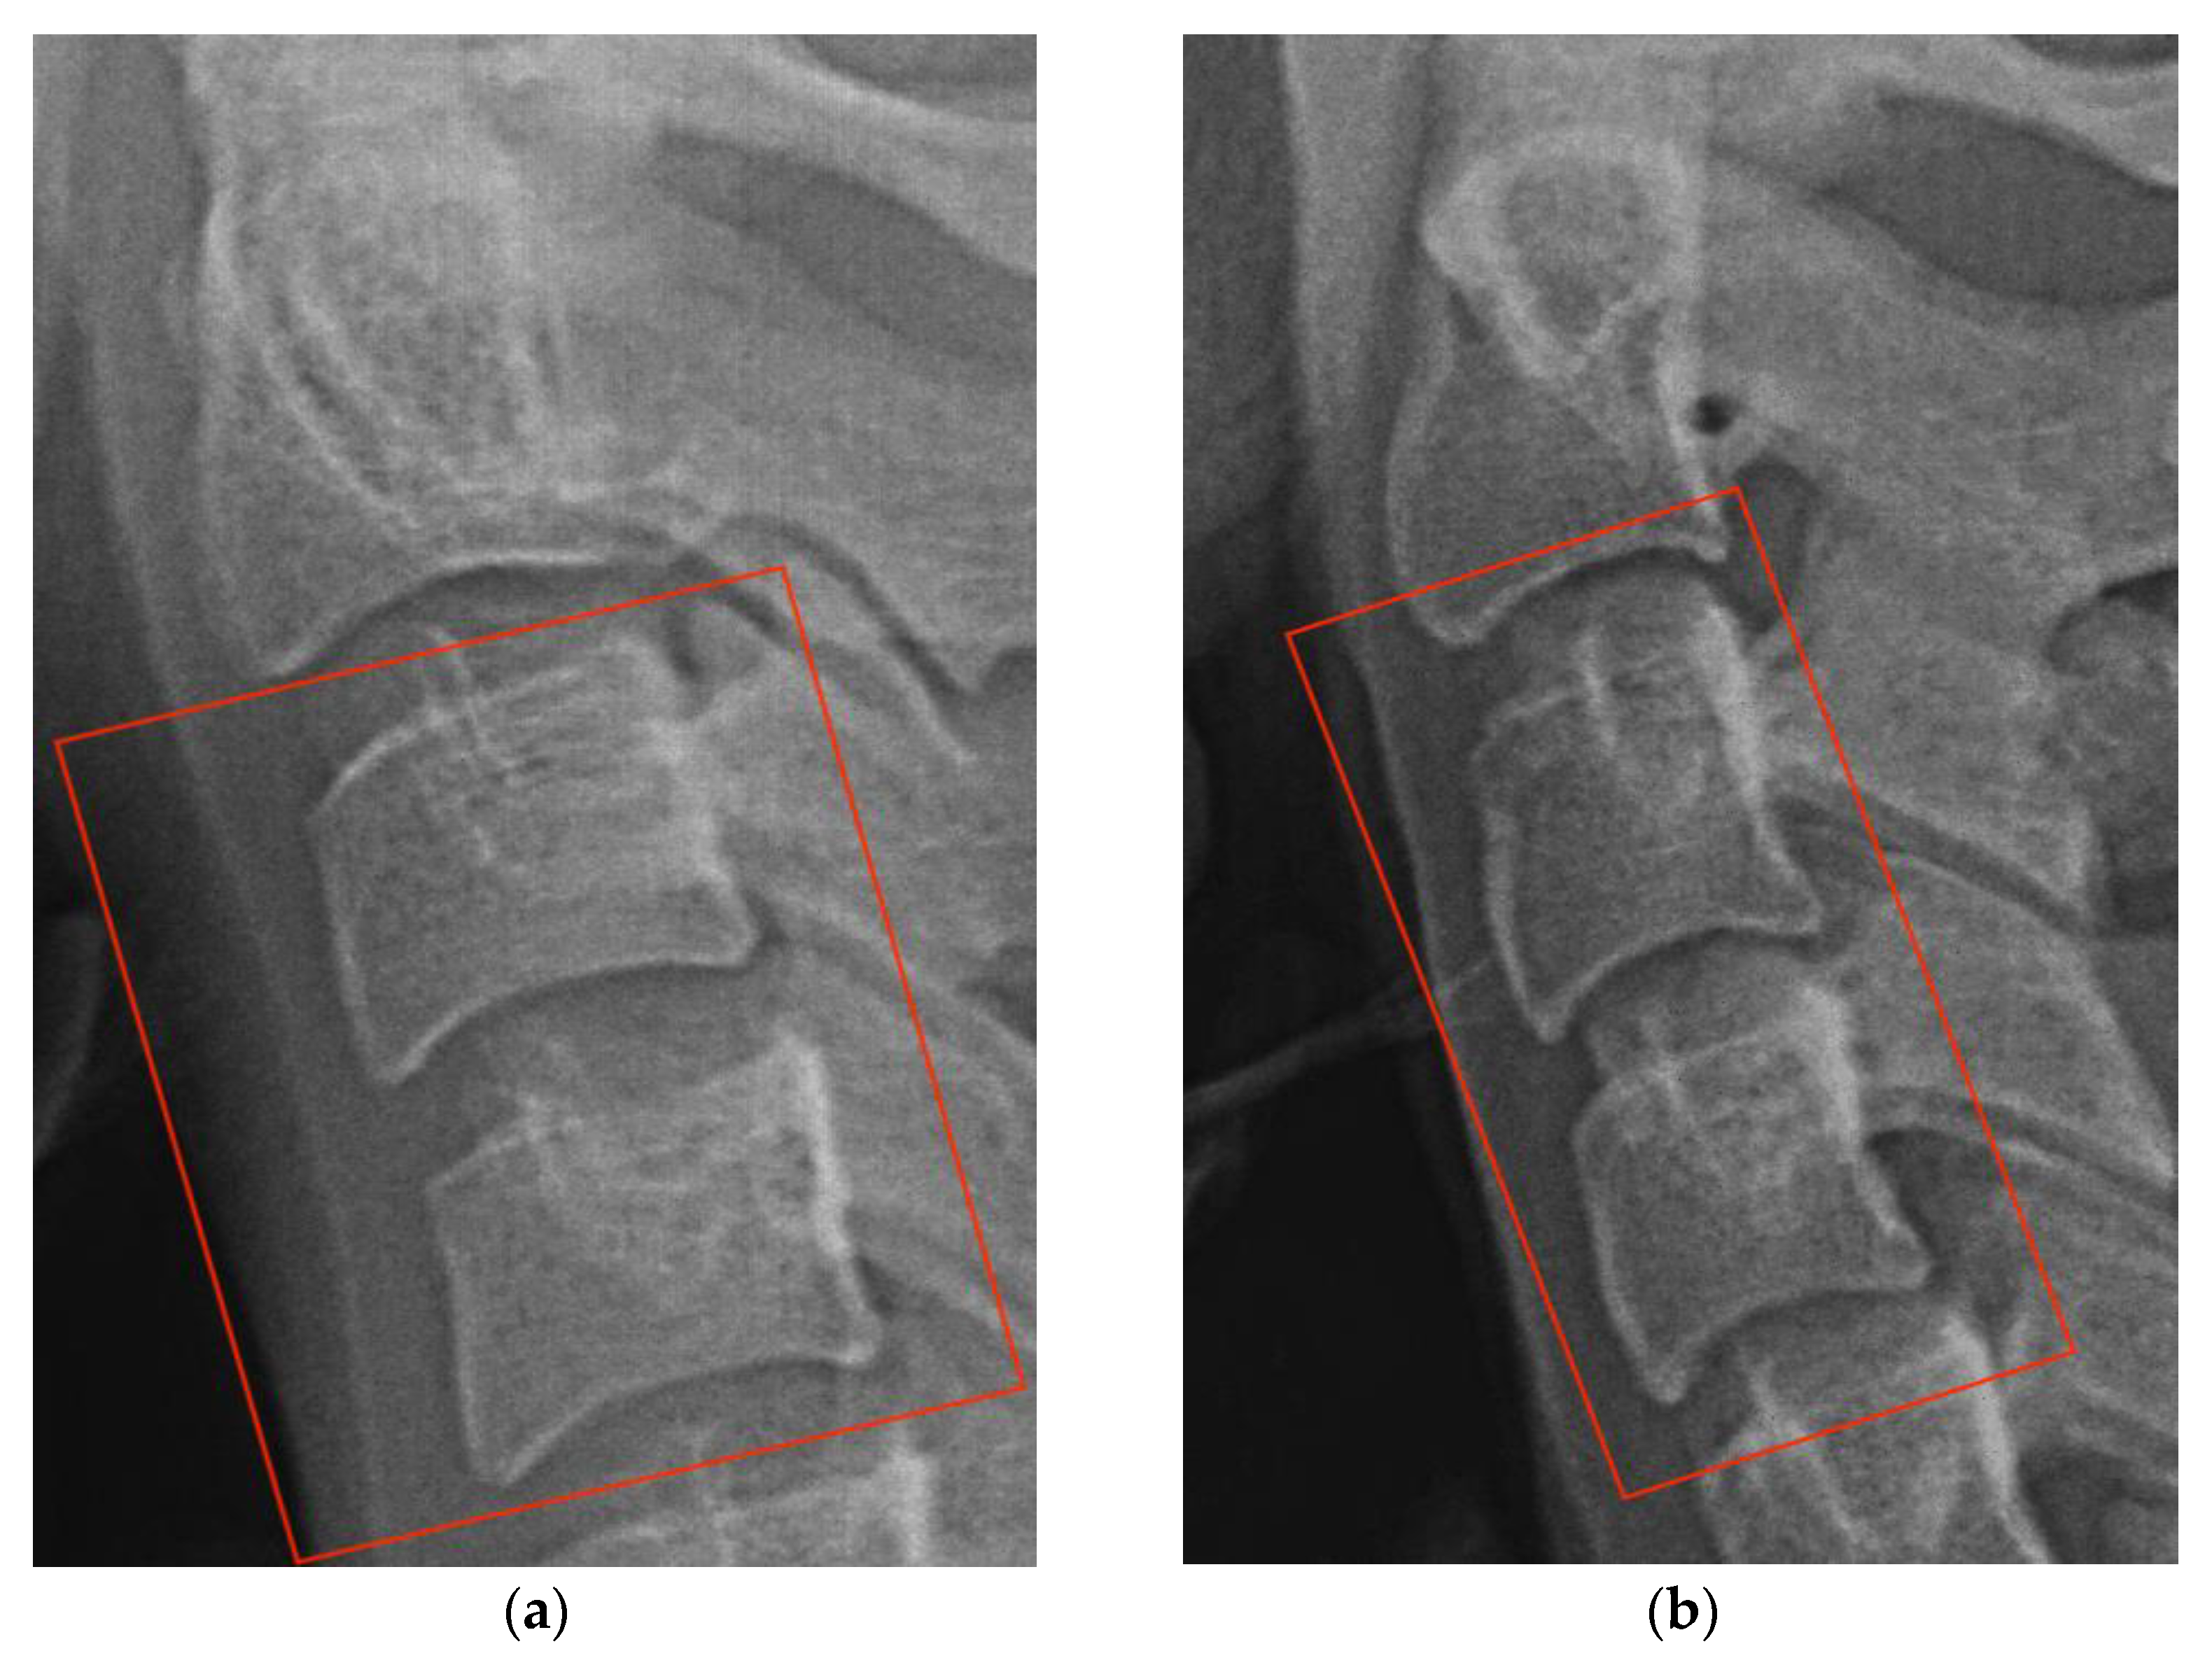

2. Cervical Vertebral Maturation Method

3.5. Dataset